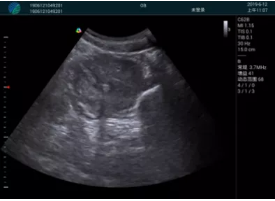

甲狀腺囊性結節(jié),囊壁鈣化,透聲好

甲狀腺囊性占位